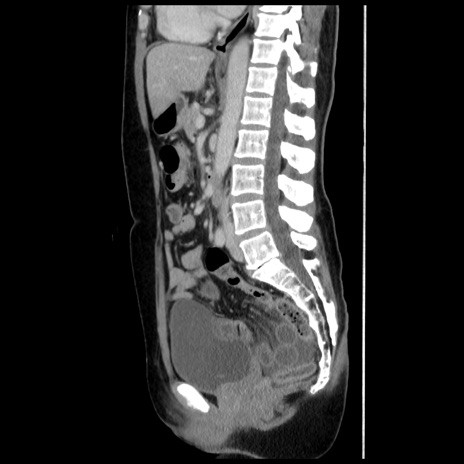

症例10(矢状断像)

【症例】 50歳代女性

【主訴】 腹痛

【現病歴】前日生レバーを食べた。今朝に排便あり。 昼前に突然発症の腹痛を生じ、当院救急外来を受診した。

【既往歴】 子宮筋腫にてで子宮全摘後

【身体所見】 意識清明、腹部:平坦、軟、下腹部やや左を中心に圧痛・反跳痛あり、筋性防御あり

【データ】WBC 7800、CRP 0.07